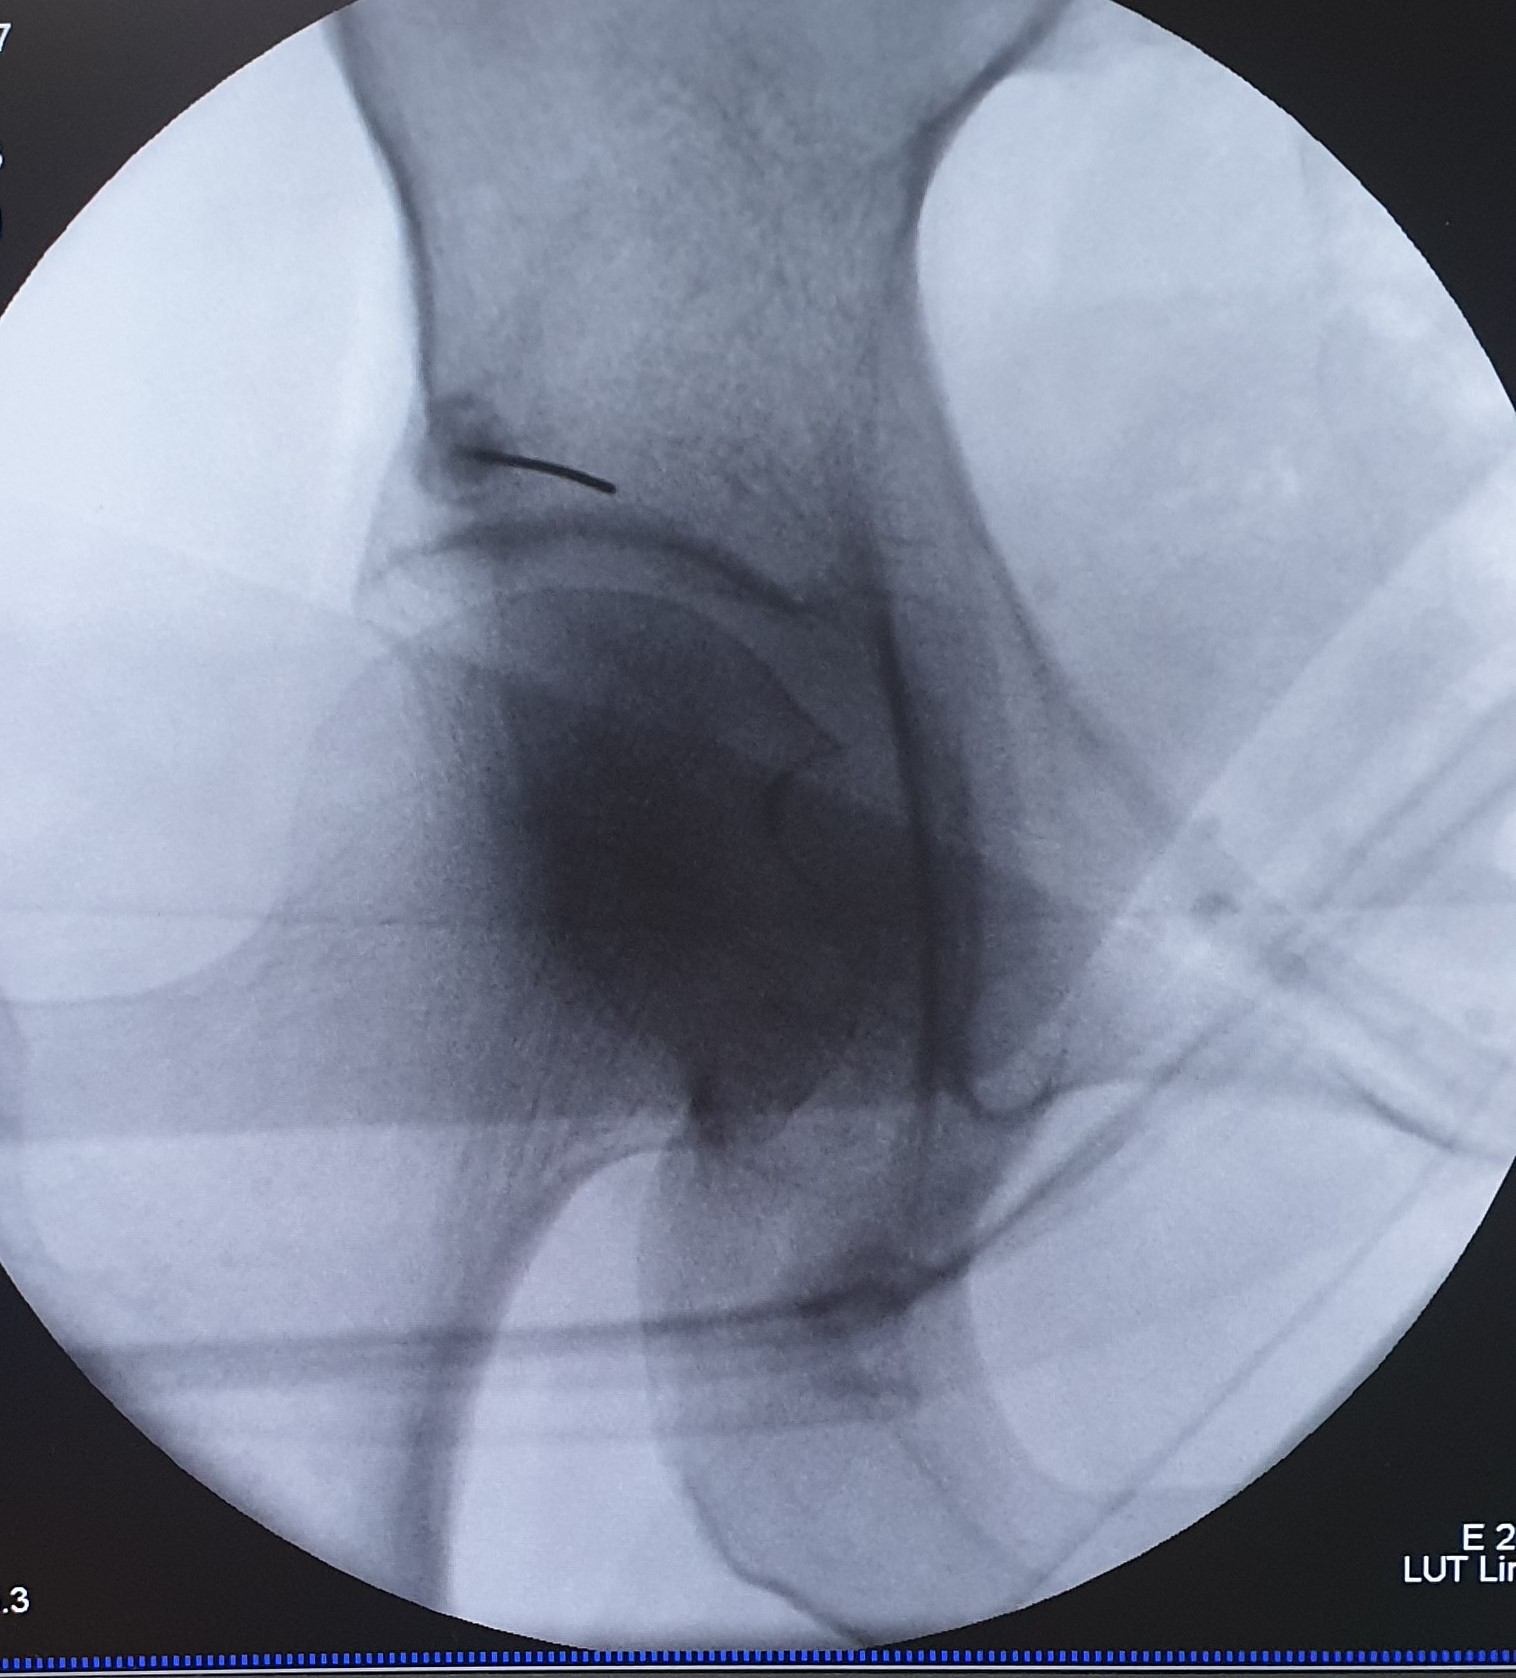

- Κατάλυση των ζυγοαποφυσιακών αρθρώσεων της κατώτερης ΟΜΣΣ και της ιερολαγονίου άρθρωσης με χρήση ραδιοσυχνοτήτων ή κρυοαναλγησίας

- Χειρουργική σταθεροποιήση ιερολαγονίου άρθρωσης